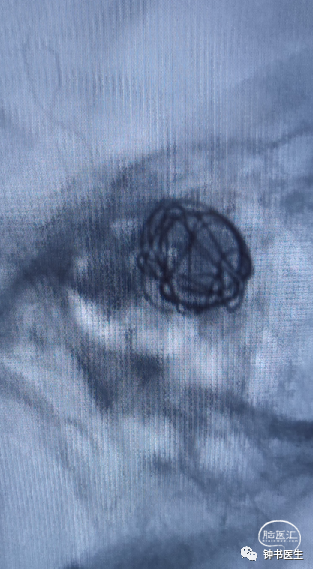

椎基底夹层动脉瘤:65Y M,脑干梗塞

术后患者无明显不适(TB 6.0X45)